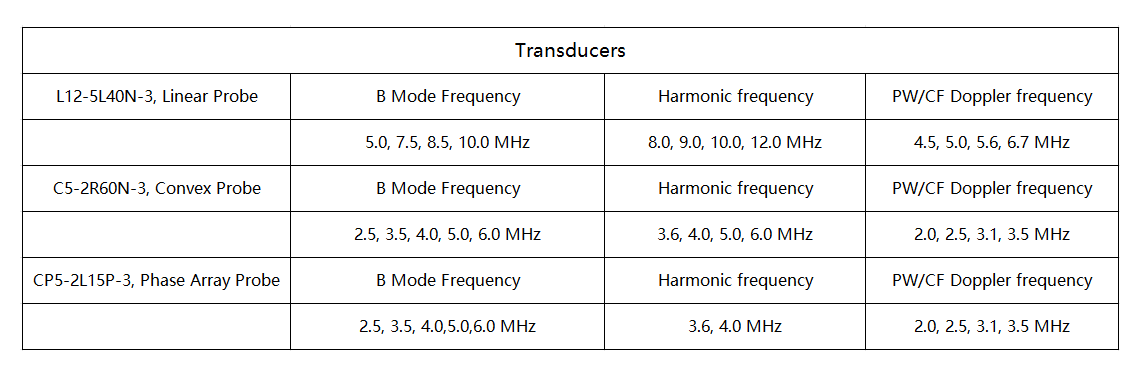

Can be connected with every terminal of iOS Android and Windows system

Battery:Removable big capacity lithium battery

Display Mode:B, M, CF, PW, PDI, DPDI, Needle Enhancement

Measure Function:OB,distance,area of a circle,Velocity,blood flow measure,fetal heart,heart rate